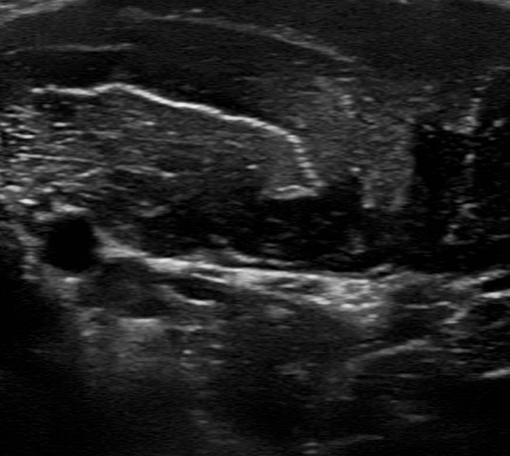

前腕~手関節部痛への超音波エコーガイド下鍼

前腕や手関節の筋・腱・神経を可視化し、細かな痛みの原因を特定。腱鞘炎や使い過ぎによる痛みに対応します。